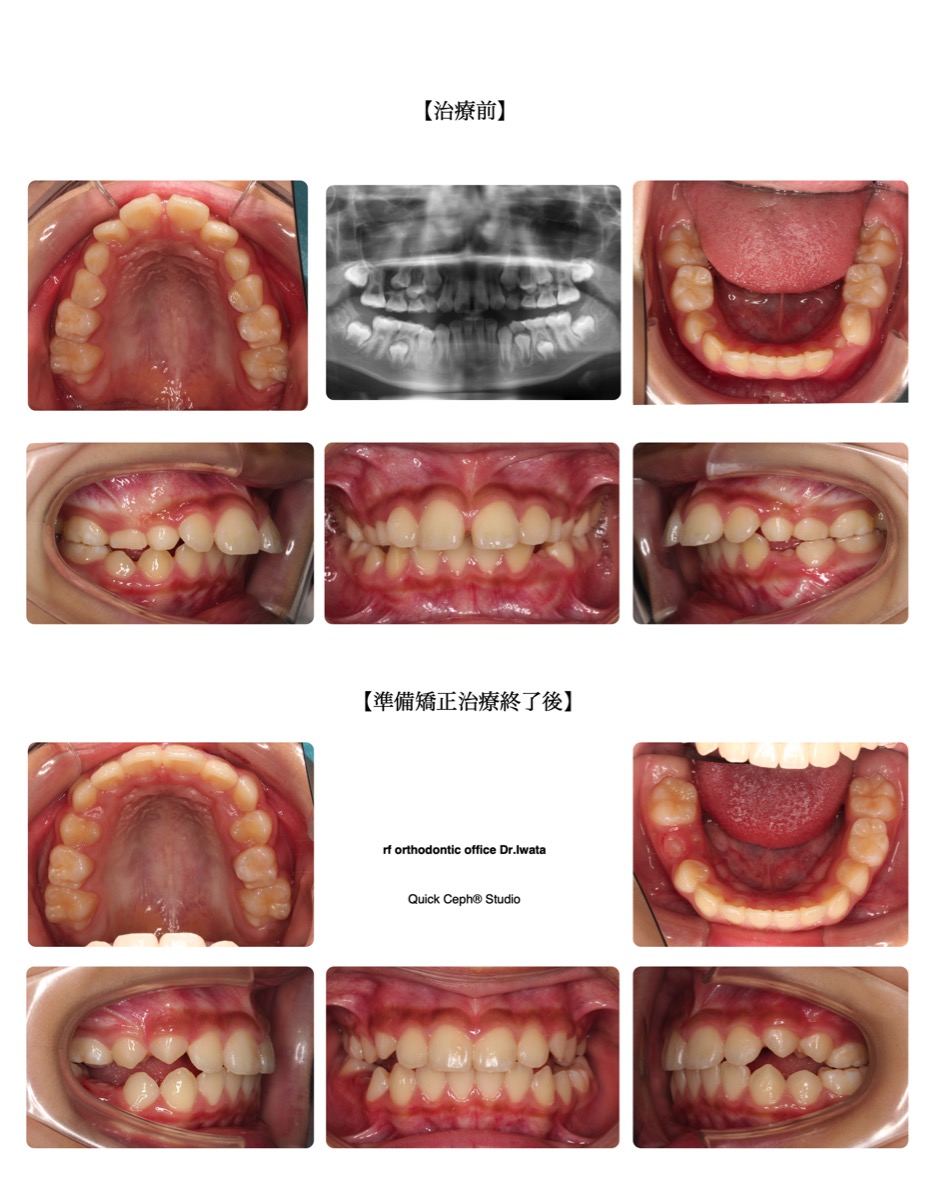

【主な症状】上顎前突(上顎前歯の突出) 正中離開 過蓋咬合

| 治療期間・回数 | 13ヶ月・5回 |

| 性別 | 女性 |

| 年齢 | 9歳 |